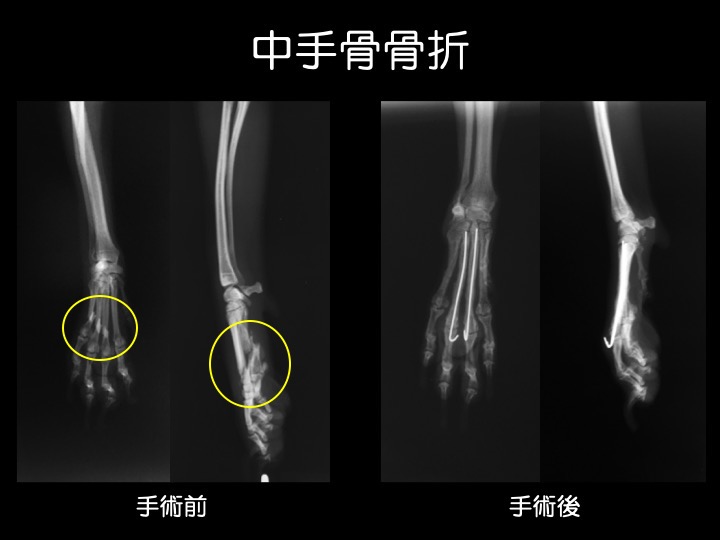

・中手骨は「手のひら」の骨で、抱っこから落下したり、人や車が誤って踏んでしまった場合などに折れるケースが多いようです。

・小型犬では骨の幅が非常に細く、手術が困難なケースもあります。